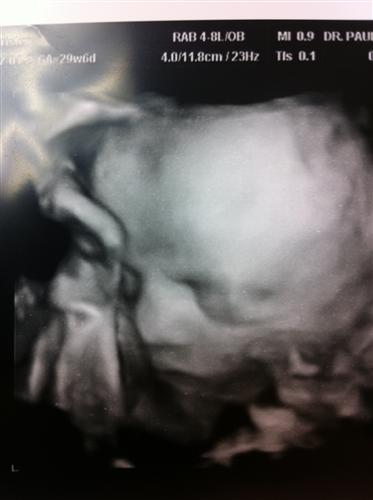

Baby!

Photo(s):

3

Click a thumbnail to view fullsize image.